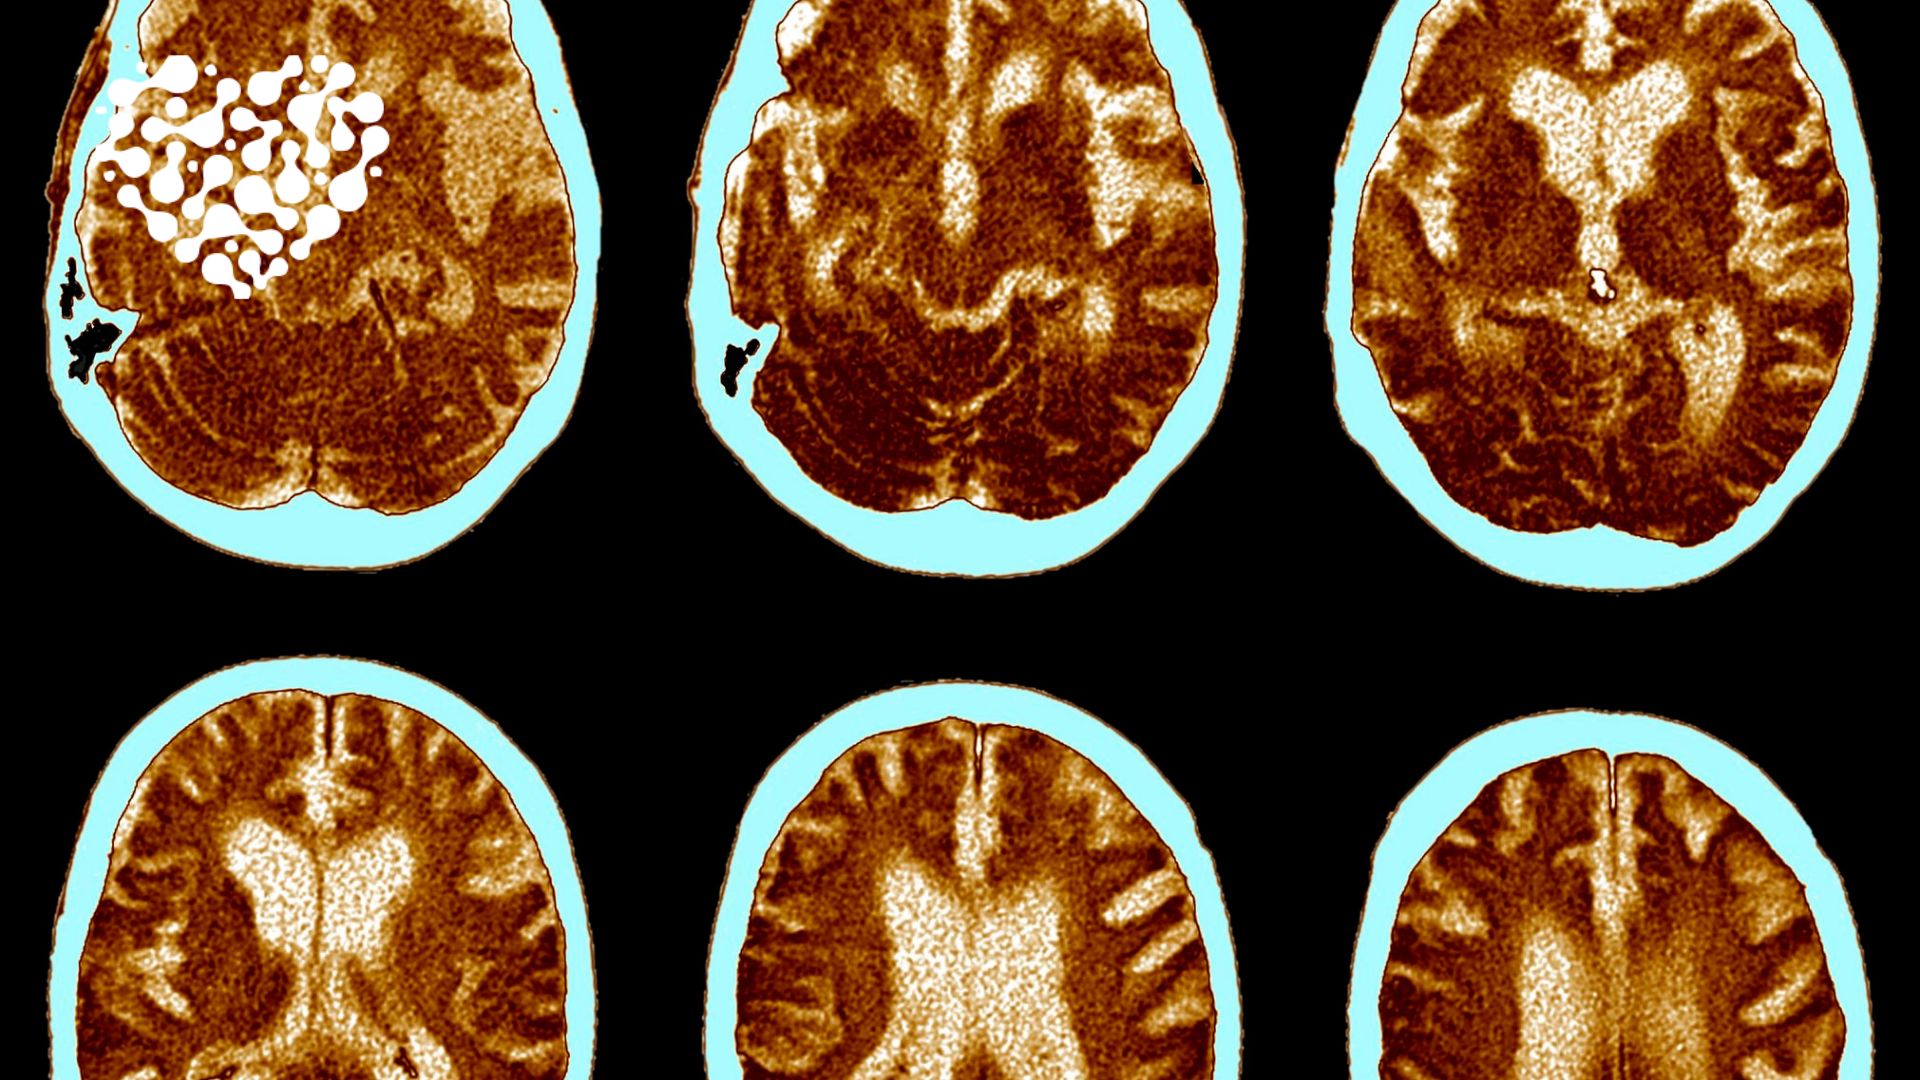

Травмы головы: что делать и когда обращаться к врачу?

Травмы головы – одна из наиболее серьезных и распространенных проблем, с которыми сталкиваются...